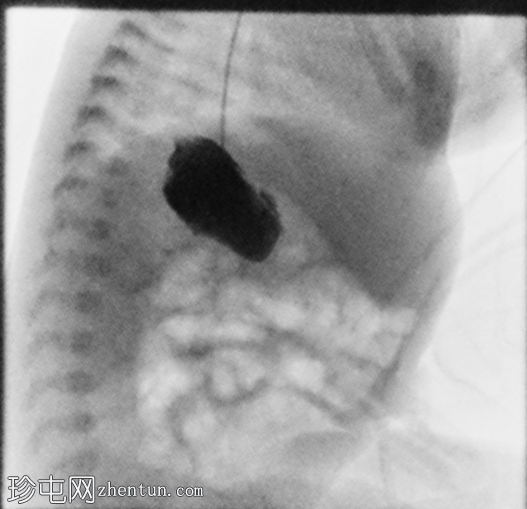

侧位

胃位于右上腹。观察到轻度中段食管反流。造影剂在近端十二指肠的延迟通过量极少,这属于异常情况。

延迟正位和侧位X线片显示肠内容物通过时间极短。

本例为腹腔内脏反位合并肠旋转不良。